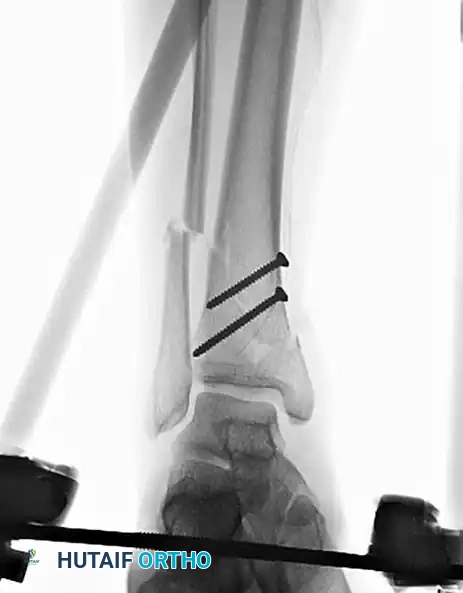

In the context of severe open fractures, interfragmentary screw fixation is an invaluable temporizing or supplementary measure. When applying a uniplanar external fixator to an open fracture, coronal plane stability can sometimes be difficult to control.

In such scenarios, large butterfly fragments or displaced metaphyseal spikes can continue to endanger the overlying soft tissue envelope. Anatomical reduction of the tibia and the strategic placement of interfragmentary lag screws can provide immediate stability as an adjunct to the external fixator.

Transfixation by Screws (ASIF) as an Adjunct

While diaphyseal fractures are rarely treated with lag screws alone due to the lack of a neutralization device (which leads to unacceptable failure rates under torsional and bending loads), transfixation by screws remains a vital adjunctive technique.

Indications in Complex Trauma

Lag screws are highly effective for the fixation of long oblique or spiral fractures (defined as having a length greater than three times the diaphyseal diameter) that extend into the metaphysis. The screws must be placed perfectly perpendicular to the fracture plane to achieve maximal interfragmentary compression and must be spaced evenly, avoiding the narrow, brittle apices of the fracture ends.